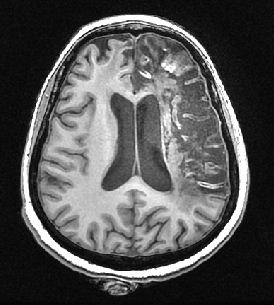

Les images anatomiques du sujet 12211 permettent de mettre en évidence un AIC au stade chronique.

L'acquisition des images a été réalisée lors du séjour du patient en ré-éducation, 6 mois après l'apparition des symptômes. Les séquences permettent de mettre en évidence un AIC carotidien droit au stade chronique (hyposignal en pondération T1 et hypersignal en pondération T2) avec atrophie du tissu cérébral de l'hémisphère droit. L'angiographie-IRM (ARM) des vaisseaux du cou montre une dissection de l’artère carotide interne droite (aspect en flamme de bougie) avec retentissement hémodynamique d’aval.

| Coupe axiale, pondération T1 |

- RMsujet12211anatpathologieAVC.img : Image en haute définition, acquise en pondération T1. Caractéristiques techniques : FOV : 512, 154 coupes ; résolution spatiale : 0,49 X 0,49 X 1,2mm3 ; TR : 7,164ms ; TE : 3,12ms ; Flip angle : 15°. Remarque : du fait de la définition de l'image, le temps de téléchargement par le logiciel est à prendre en compte (environ 2min pour une connexion à 3Mo)